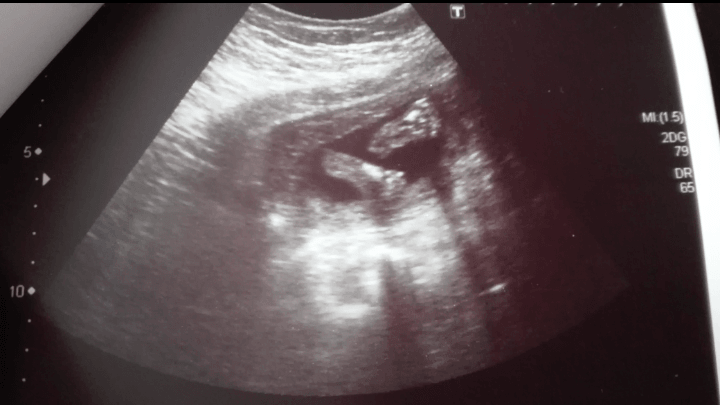

Ja dzisiaj zaczynałam dzien od USG (podobno połówkowego) na NFZ. Trwało może 3 minuty. Lekarz powiedział, że wszystko ok, ale niedosyt straszny po wizycie...

Dowiedziałam się znów, że na 100% będzie laseczka, bo cyt. "widać cipkę" (myślałam, że się przesłyszałam i mówię, że co? A ten, no siusiaka to tu nie ma) oraz, że dziecko ma długie nogi, po czym lekarz spojrzał na mnie leżącą i mówi, na pewno po mamie (tu akurat obrosłam w piórka momentalnie). Jak to ujął, niesamowicie zgrabny ten bobas. Akcja serca prawidłowa, ok 140/min, serce czterojamowe, pęcherz moczowy i żołądek widoczne. Obraz trzech naczyń w śródpiersiu prawidłowy. Pępowina trójnaczyniowa. Poziom wód płodowych w normie i wg USG jest o 3 dni starsze, a waży 402g <3 do tego mam urocze zdjęcie stópek Maluszka

Stópki moje Maluskie :)